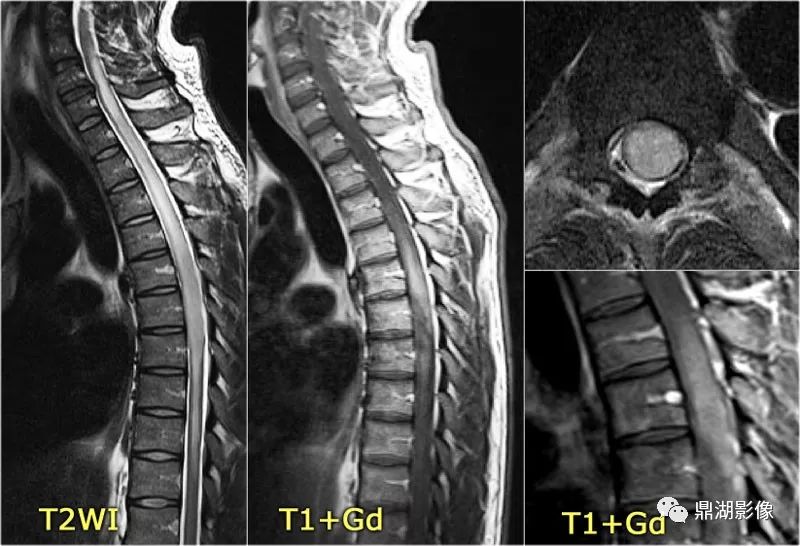

脊髓节细胞胶质瘤1例mr影像解析